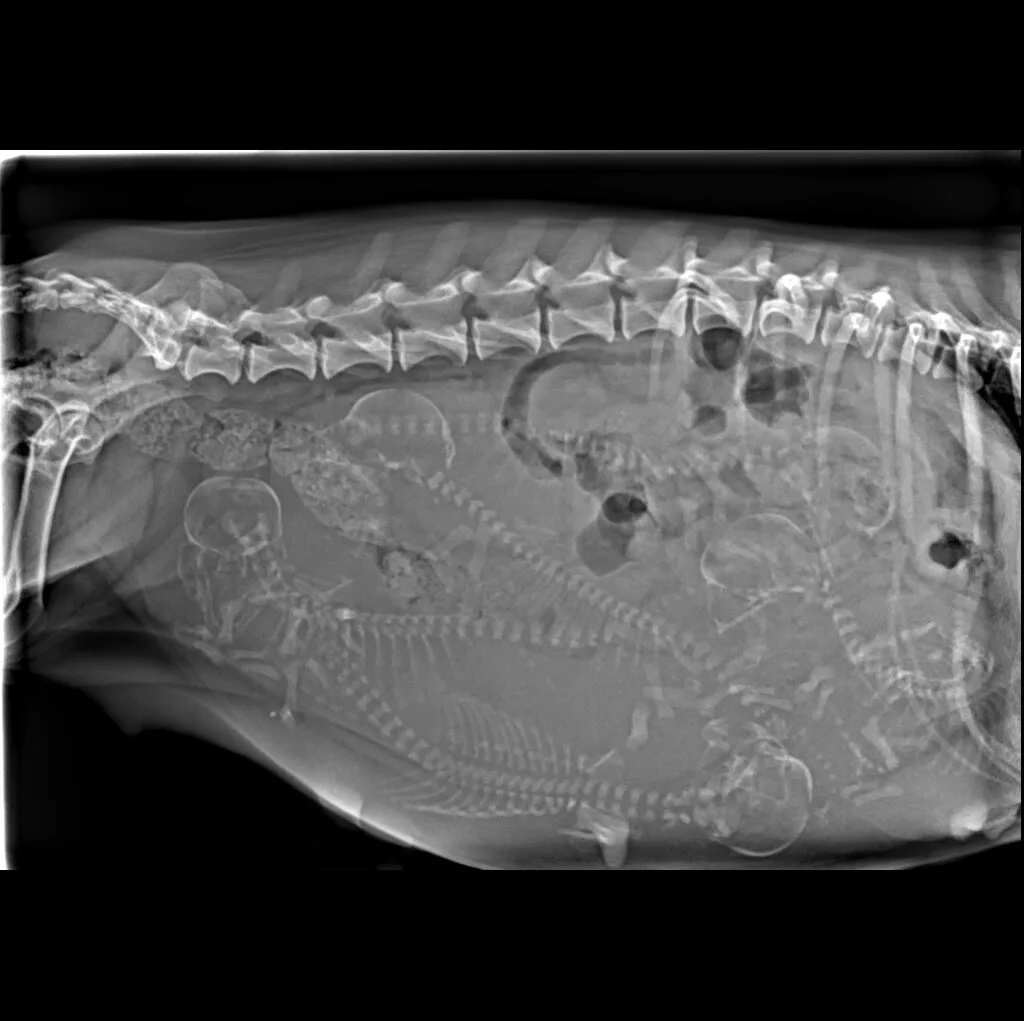

At Grand Ave. Pet Hospital, we utilize digital radiography to diagnose and monitor a wide range of medical conditions in pets. Digital X-rays provide clearer images, faster results, and safer radiation levels, ensuring the best possible care for your furry companion.

Digital radiography offers superior imaging quality and precision compared to traditional X-ray techniques. It allows us to detect hidden health issues early, leading to faster and more effective treatments.

🔹 Abdominal & Gastrointestinal Issues – Detecting obstructions, tumors, or organ abnormalities